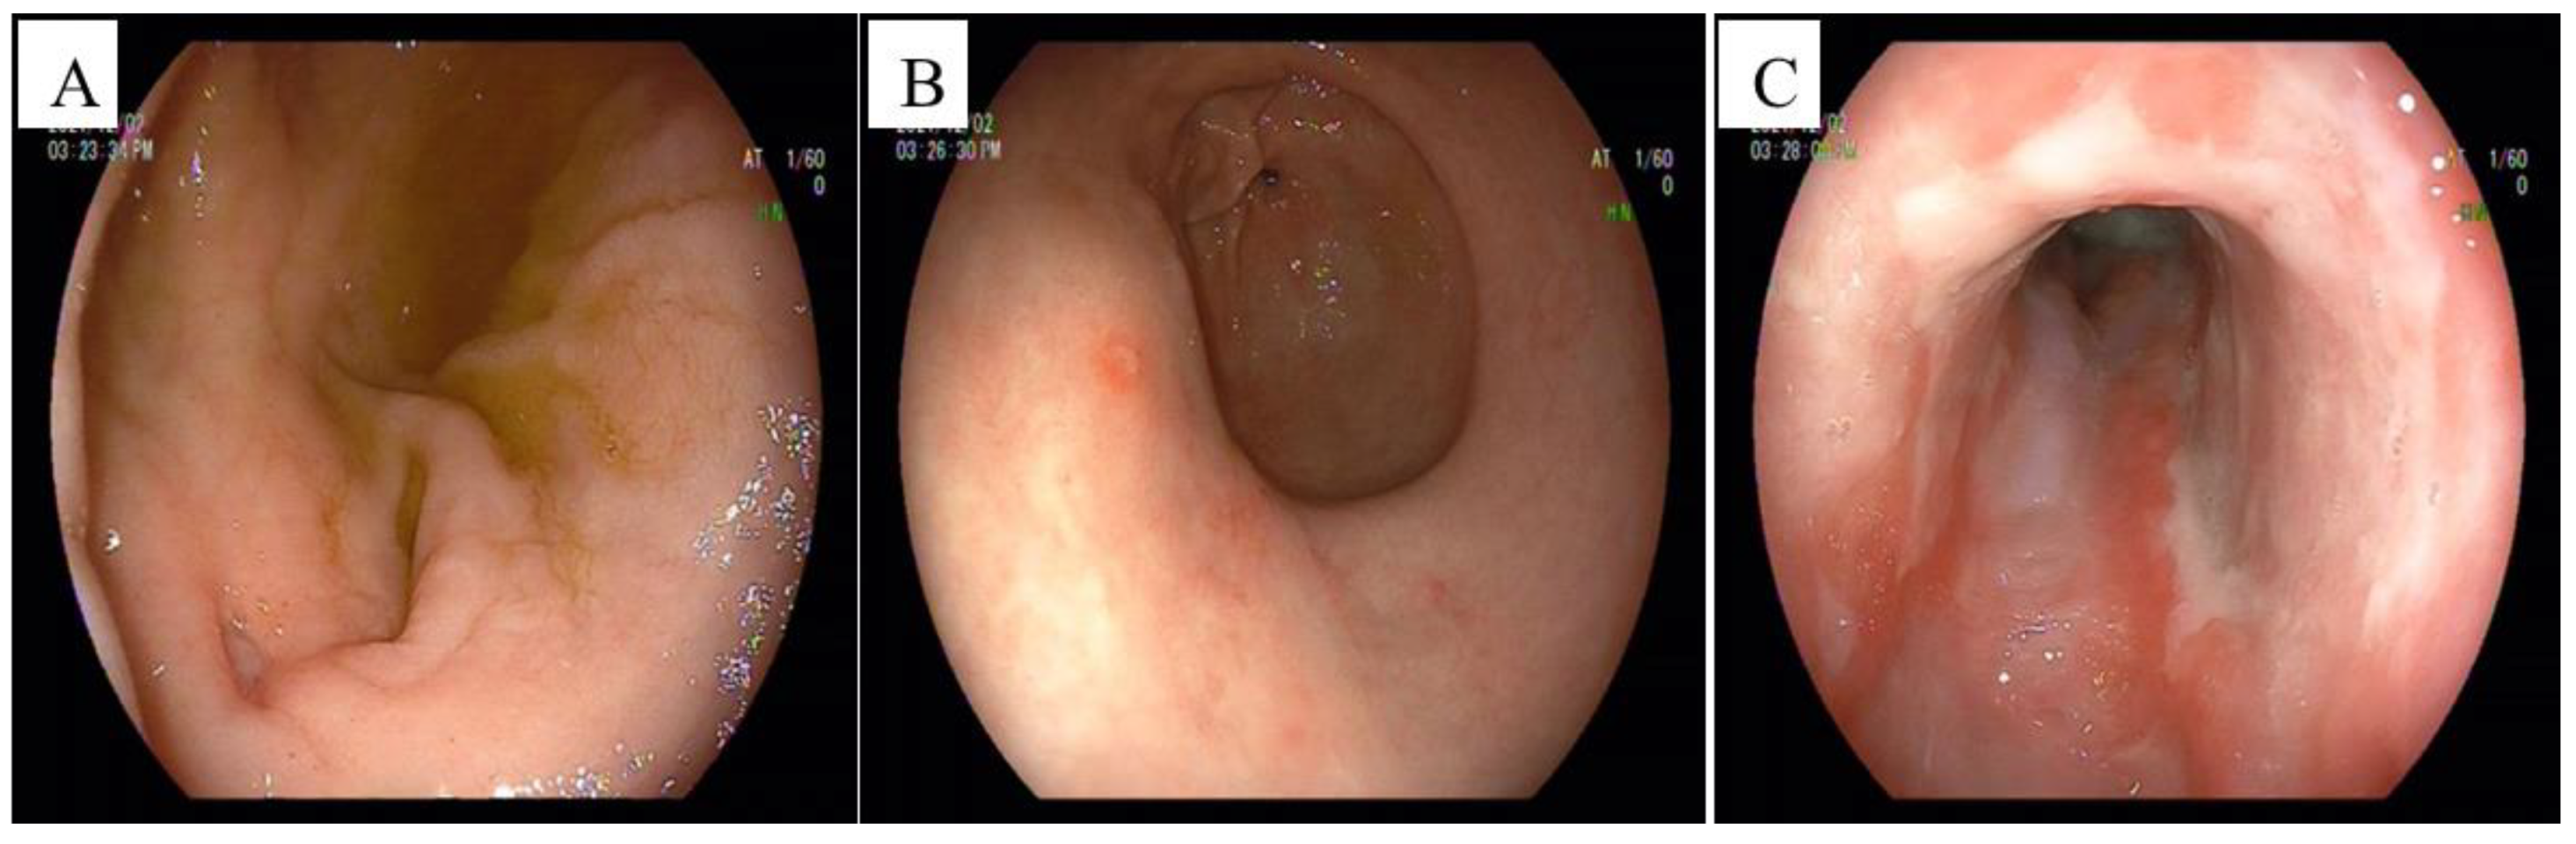

2. Case Presentation